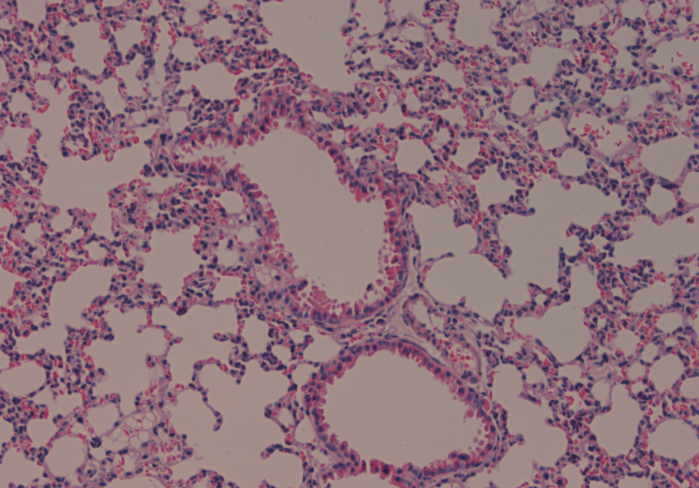

[求助] 组织切片-肺

请帮忙分析两张肺组织切片,拜托了

组织切片-肺

组织切片-肺-1